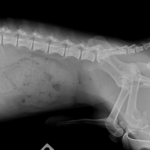

腹部 X 線写真では、肥大した前立腺が下腹部の軟組織塊として観察される。通常のサイズは骨盤入口の幅の 50% 未満である。慢性前立腺炎患者の中には、実質の石灰化が見られる場合もある。腰下リンパ節に腫大があれば前立腺の腫瘍を疑う必要がある。